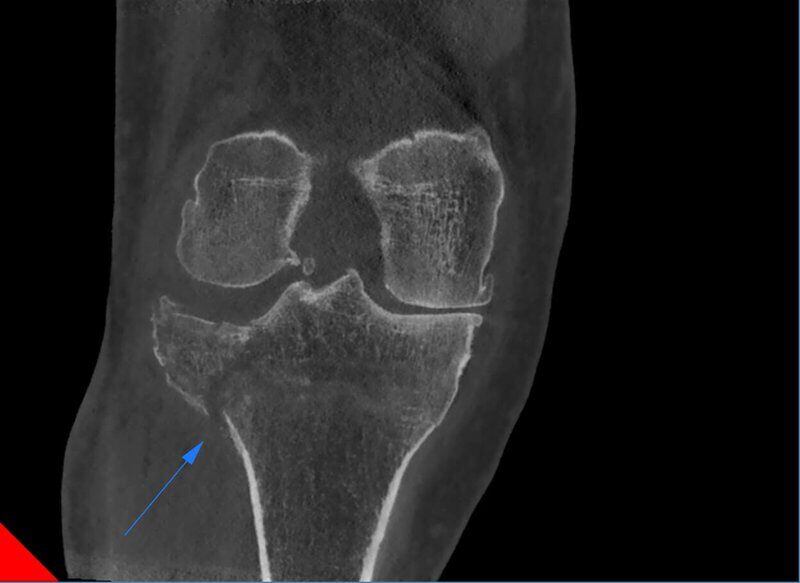

Frattura multipla ginocchio